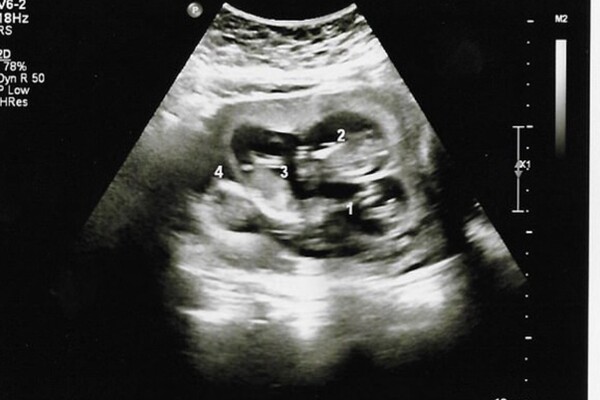

Ban đầu, Danielle chỉ nghĩ mình mang thai đơn. Cô không có biểu hiện đặc trưng của đa thai nên hoàn toàn yên tâm. Tuy nhiên, khi thai được khoảng 6 tuần, những cơn đau bụng dữ dội khiến cô phải vào viện cấp cứu. Tại đây, bác sĩ thông báo cô đang mang song thai. Dù bất ngờ, Danielle vẫn khá bình tĩnh vì trong gia đình cô từng có tiền sử sinh đôi.